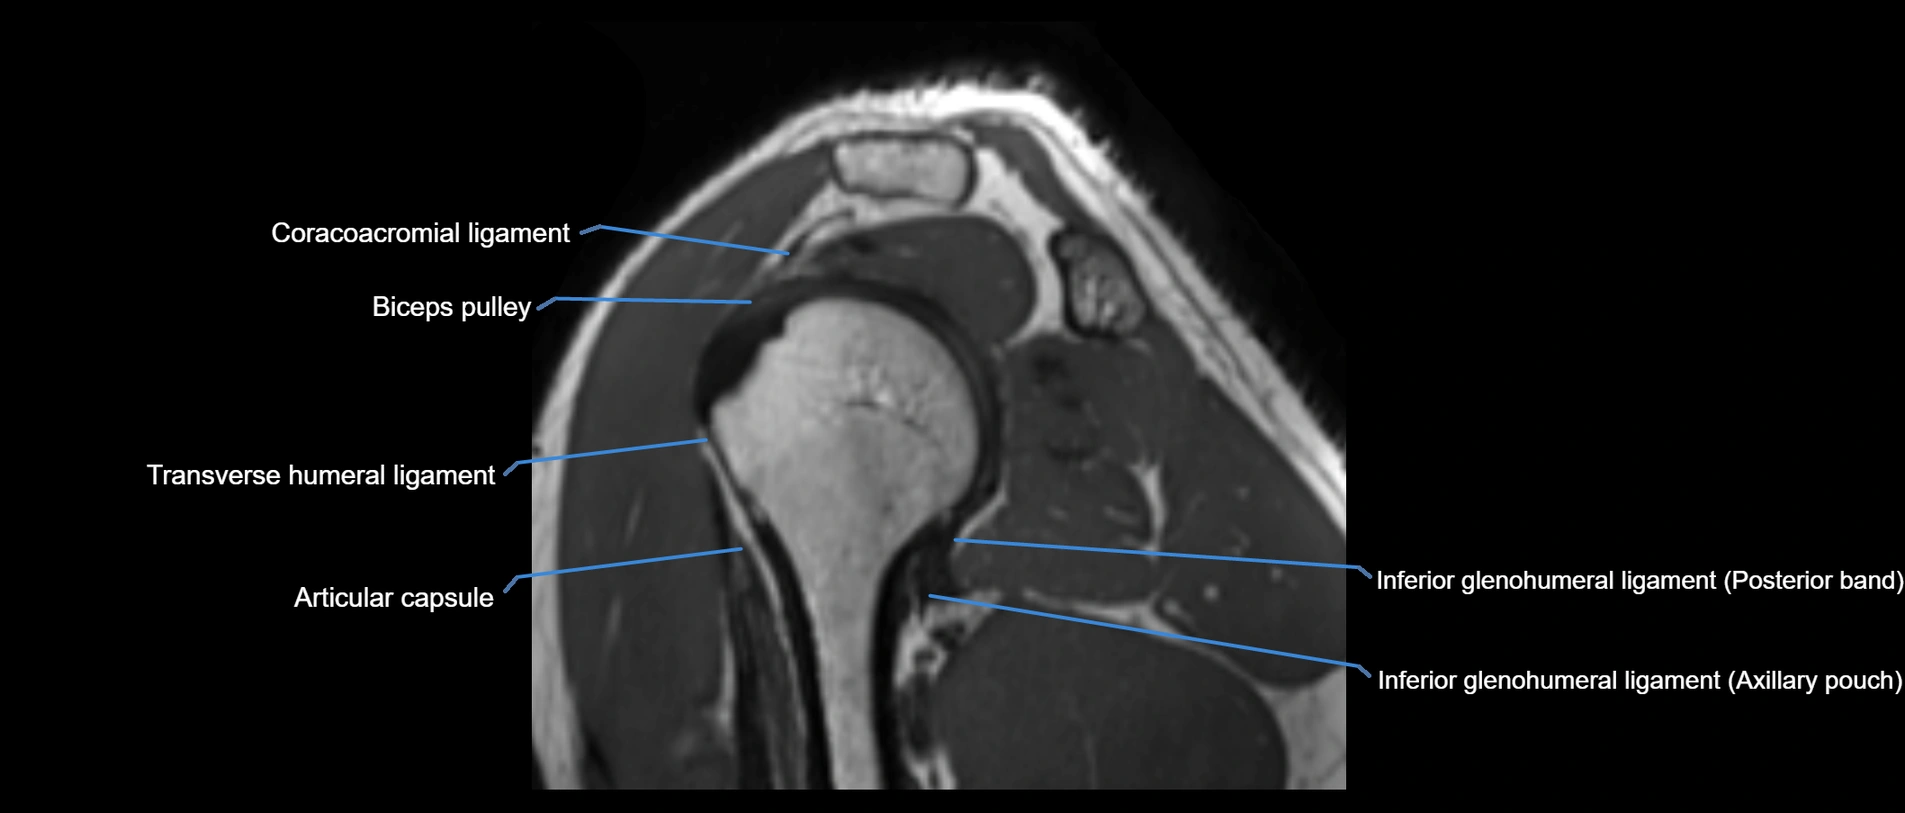

MRI images

image

MRI Appearance

• T1-weighted images:

• Normal ligament: Low signal (dark linear band) spanning acromion to clavicle.

• Surrounding fat planes: Bright, delineating the ligament clearly.

• Marrow of clavicle and acromion: Bright due to fatty content.

• Tears: Discontinuity or irregular thickening with intermediate-to-bright signal.

• Chronic injury: Thinning, fraying, or irregular low-signal fibers with adjacent scarring.

• T2-weighted images:

• Normal ligament: Low signal, homogeneous.

• Partial tear or sprain: Focal hyperintensity or thickening.

• Complete tear: Discontinuity with fluid-bright gap between clavicle and acromion.

• Associated edema: Bright signal in distal clavicle or acromion marrow.